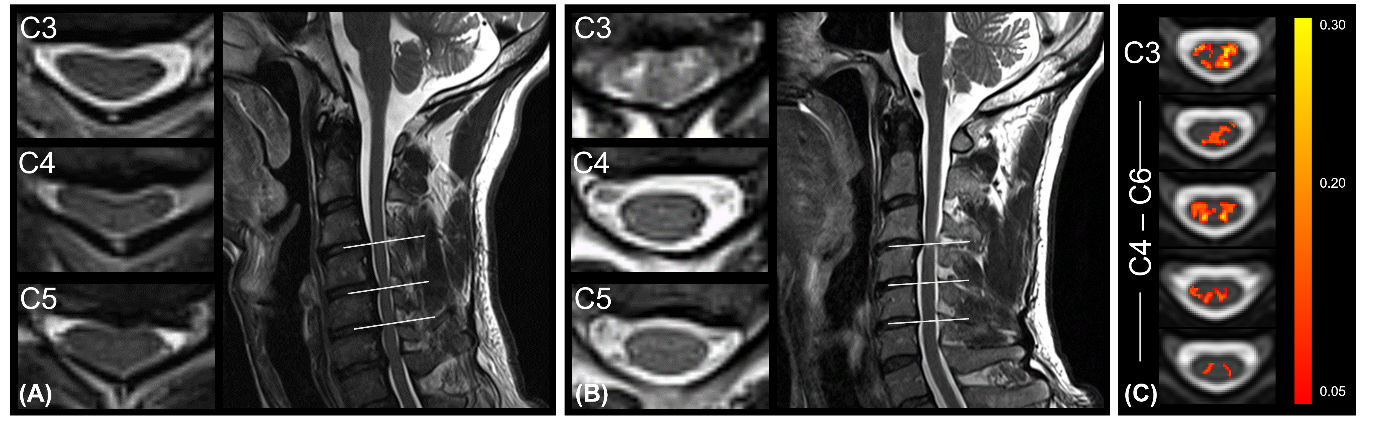

Eight DCM patients showed radiological evidence of cervical myelopathy (n=2 at C3/C4, n=2 at C4/C5, and n=4 at C5/C6) (Figure 1B). The lesion frequency maps indicated higher frequency of myelopathy in GM at C3-C5 levels in the DCM group (Figure 1C). Atrophy was observed in WM (Δ = -9.7%; p = 0.006) and GM (Δ = -6.8%; p = 0.005) of DCM patients (Figure 2), which is in agreement with previous findings27. Perfusion maps, averaged across subjects, depicted the distribution of the IVIM parameters in different ROIs (Figure 3). $$$F$$$ was greater in GM compared to WM in both cohorts, in alignment with previous studies15,28,29. The maps visually suggested a gradient of $$$F$$$ in GM in DCM, decreasing from C1 to C3 (Figure 3B). While $$$D^*$$$ and blood flow ($$$F$$$∙$$$D^*$$$) were reduced in GM, cord region mainly affected by DCM1, only $$$D^*$$$ decreased in WM of DCM (Figure 4B-C). Of note, a positive correlation was found between $$$F$$$ and GM area (Figure 5). Although group interaction (HC ~ DCM) was not significant, post-hoc analysis indicated that the correlation was mainly driven by DCM (R = 0.69, p = 0.02), while no correlation was observed in HC (R = 0.04, p = 0.90). This suggests a possible alteration in microvasculature volume in GM related to the atrophy observed in DCM patients.

Figure 1: Overview of the site of compression in DCM patients (A) without and (B) with radiological hyperintensity myelopathy. (C) Frequency map of radiological hyperintense signal along the cord of DCM patients with cervical myelopathy (n = 8) overlaid on the PAM50 template.